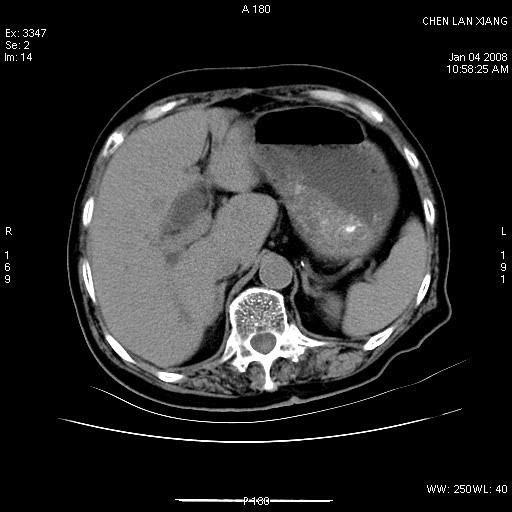

女,76岁,腹痛3-4天,b超示:肝内实性肿物,胆囊强回声,胆总管扩张.

考虑:1、胆总管下端结石伴梗阻性肝内外胆管扩张(肝左叶外侧段肝内胆管多发结石、胆管炎);

2、肿囊癌累及肝,不除外 黄色肉芽肿性胆囊炎。

1 胆总管末端结石伴肝内胆管结石,肝内外胆管扩张。2 胆囊扩大,胆囊壁不规则增厚,内见软组织密度影。考虑:慢性胆囊炎,不除外胆囊癌!

标题: 肝右叶病灶

胆囊癌侵犯肝右叶?

1)胆囊癌伴肝脏转移。2)胆总管下端结石、肝内胆管结石伴肝内外胆管扩张。